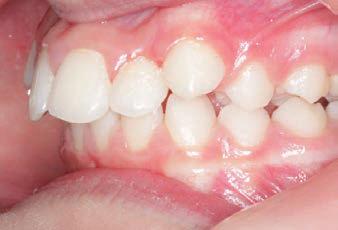

CLASS II DIV.1 - Marra

INITIAL - 4/4/18